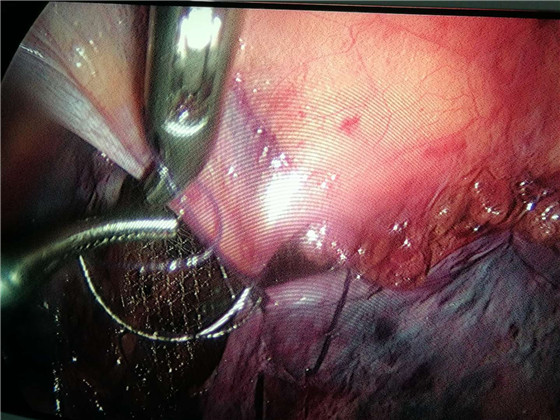

近日,我院普外科成功开展首例腹腔镜下腹股沟疝修补术。患者术后恢复良好,目前已治愈出院。此项手术的顺利开展不仅拓宽了我院腹腔镜的运用范围,也标志着我院微创外科水平又有了新的突破。

腹股沟疝是外科的常见病、多发病,手术是治疗成人腹股沟疝唯一有效的方法。与传统的腹股沟无张力疝修补术相比,微创的腹腔镜手术,创伤小,疼痛轻,恢复快,术后次日就可以进行日常生活,3-5天左右即可出院。为开展此项技术,我院选派了蒋结志和吴成成主治医师分别前往安徽省立医院和浙江邵逸夫医院进修学习微创外科手术。此次手术,在高有龙主任指导下,蒋结志主治医师和吴成成主治医师通力合作,成功完成了我院首例腹腔镜疝无张力修补术。